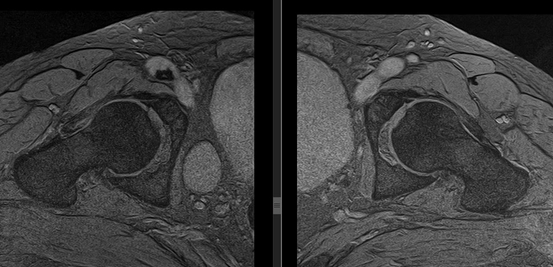

Рисунки 1,2. МР-картина артроза тазобедренных суставов с наличием отека костного мозга дистрофического характера в верхне-наружных отделах вертлужной впадины справа

Рисунок 3. МРТ тазобедренных суставов в косо-аксиальной плоскости.

Суставной хрящ головки бедренной кости и правой вертлужной впадины с обеих сторон однородной структуры, неравномерной толщины, целость его не нарушена. Головка бедренной кости сферичная, шейка не укорочена, не утолщена.